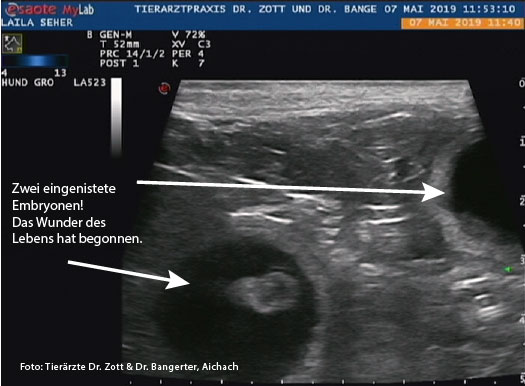

07. Mai 2019

Ultraschall beim Tierarzt.

Ein Herz! Man sieht ein kleines Herz schlagen!!!

JUHU! Wir sind schwanger!

Die Gesamtzahl der Welpen ist derzeit noch nicht feststellbar.